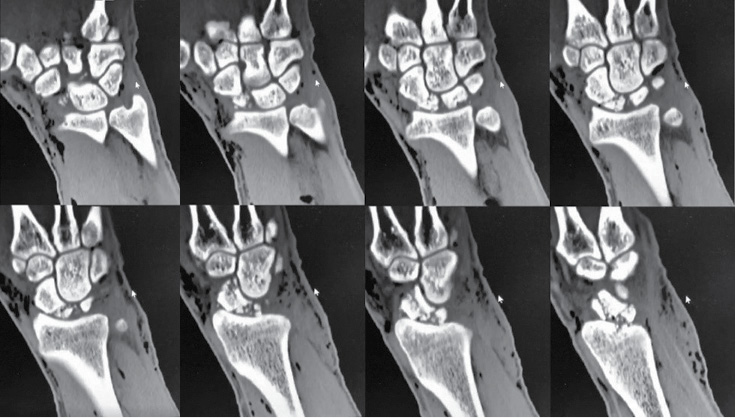

2 pav. Kairiojo riešo trijų krypčių rentgenogramos po operacijos: priekinė rentgenograma (A), šoninė rentgenograma (B), įstrižinė rentgenograma (C)

Operacijos metu atliktas pjūvis kairiosios plaštakos nugariniame paviršiuje tarp trečiojo ir ketvirtojo tiesiamųjų sausgyslių kompartmento laivelio projekcijoje. Naudojant bukąją ir aštriąją disekciją, pasluoksniui pasiektas kaulas. Rastas nesugijęs laivelio lūžis. Pašalintos proksimalinio laivelio segmento lūžgalių skeveldros, distalinė laivelio dalis rezekuota iki gyvų audinių. Vėliau atliktas apie 5 cm ilgio skersinis pjūvis ties VI dešiniojo šonkaulio krūtinkauliniu galu (mokslinėje literatūroje aprašoma atvejų, kai rekonstrukcijai naudojami V–IX šonkaulių osteochondriniai fragmentai [22, 24, 25]). Naudojant bukąją disekciją, pasluoksniui pasiektas ir nuo aplinkinių audinių, antkaulio ir krūtinplėvės atpreparuotas šonkaulis, atlikta dalinė jo rezekcija. Paimtas apie 3 cm kaulinės ir kremzlinės šonkaulio dalies fragmentas, kuris toliau formuotas pagal laivelio kaulinio defekto formą. Atsižvelgta į rekomendacijas, kad, formuojant transplantatą, jam fiksuoti ir funkcio­nuoti būtina palikti bent 2–3 mm storio šonkaulio kaulinio audinio ir 5 mm šonkaulio hialininės kremzlės [22, 24]. Autotransplantatas perkeltas į proksimalinį laivelio galą, fiksuotas dviem Kiršnerio vielų atkarpomis (žr. 2 pav.). Pjūviai pasluoksniui užsiūti, kairioji plaštaka imobilizuota gipso longete 3 mėn.